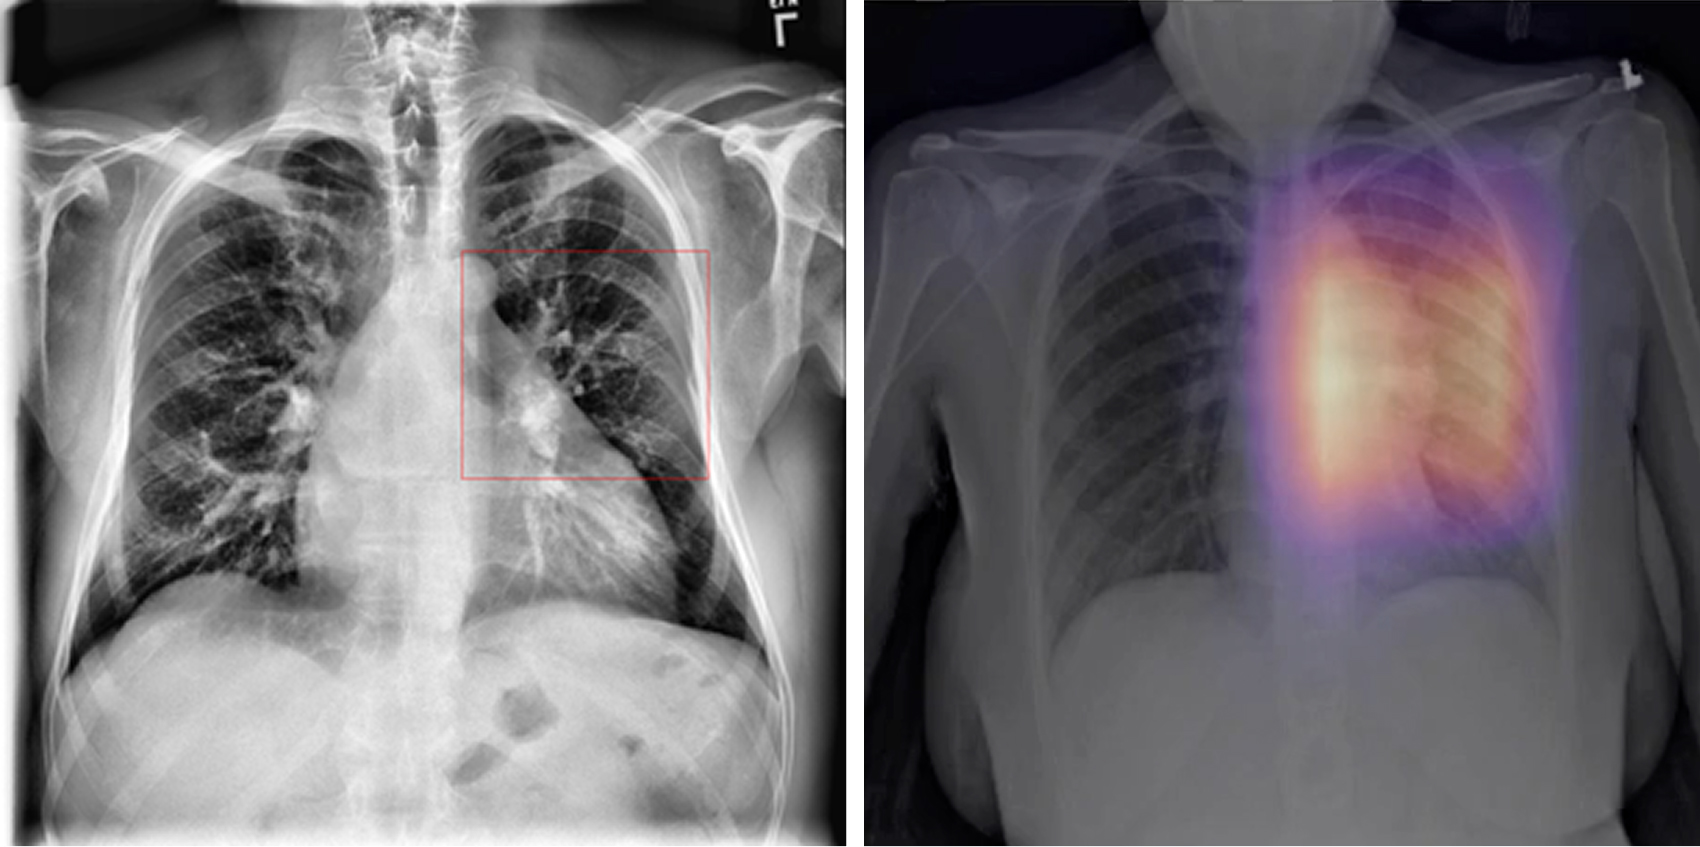

For images flagged as abnormal, a Faster R-CNN model highlights suspicious regions within the lungs. Bounding boxes and heatmaps focus attention on nodules, opacities, masses, and other radiographic abnormalities.